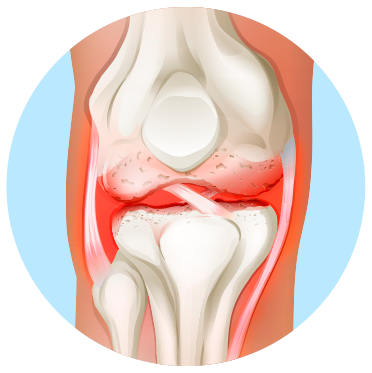

КОЛІННИЙ СУГЛОБ УРАЖЕНИЙ ОСТЕОАРТРОЗОМ

Залежно від вираженості клінічних проявів виділяють три стадії гонартрозу: від першої, за якої болі в суглобі виникають періодично після навантажень, до третьої, важкої стадії артрозу, коли суглоб значно зруйнований, а болі стають практично постійними.

На початковій стадії гонартрозу зміни на рентгенограмах можуть бути відсутніми. Згодом визначається звуження суглобової щілини й ущільнення субхондральної зони. Суглобові кінці стегнової й особливо великогомілкової кістки розширюються, краї виростків стають загостреними.